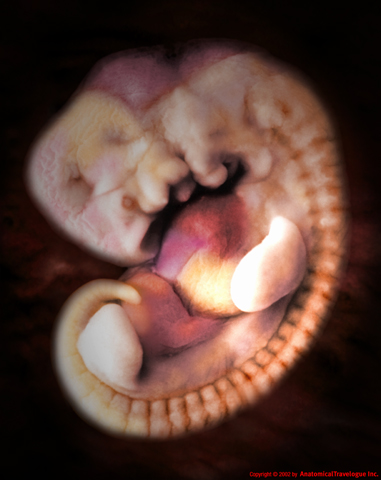

Entro la fine della settima settimana, l’embrione raddoppia la sua lunghezza crescendo da 4, 5 millimetri a 11, 13 millimetri circa. Adesso è della dimensione di un lampone. La testa è sproporzionatamente più grande del resto del corpo, e le macchie scure sono i futuri occhi e narici. Il prosencefalo è diviso in due parti che sono i due emisferi cerebrali, dove un centinaio di cellule nervose sono create ogni minuto.

La settima settimana di gravidanza